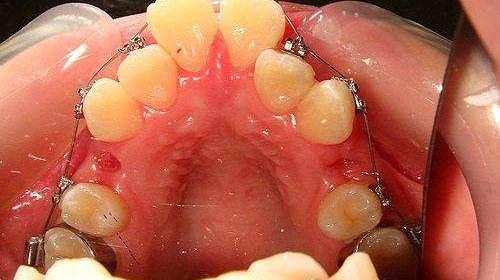

6岁到12岁的孩子处于替牙期,由于乳牙恒牙先后脱落萌出会导致暂时性牙齿不齐,如果只是简单的牙齿拥挤的情况,后期会在发育中自行调整。但是恒牙如果不能正常萌出或是因为咀嚼刺激不足导致颌骨发育不完全造成的恒牙萌出不整齐,那就需要尽早矫正治疗。

双排牙